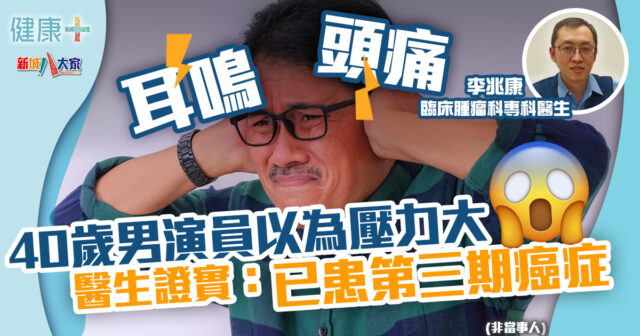

顏國樑因癌症併發肺炎,享年71歲。顏國樑於2022年與「順嫂」梁葆貞現身TVB台慶,並自揭患上第三期鱗狀細胞癌,低音聲帶被腫瘤壓住導致變聲。顏國樑一直接受化療及免疫治療,病情一度好轉,上月還攜同老婆霍潔貞現身節目,豈料25日驚傳死訊。

顏國樑早前在2022年現身TVB台慶時,自揭患上第三期鱗狀細胞癌,腫瘤導致他的聲帶失去低音。及後他於年初接受好友鄧英敏的YouTube頻道訪問,稱已三次踏入鬼門關,當中兩次幸得老婆霍潔貞救回一命,一直抱住感激太太之情積極抗癌。鄧英敏接受媒體訪問時,透露顏國樑在本月20日已經因氣促入住,還計劃今晚(27日)前往醫院探望顏國樑,對突如其來的噩耗十分婉惜。

鱗狀細胞癌

「鱗狀細胞癌」其實是從顯微鏡下觀察到的癌細胞形態,非單一部位發現的癌症。鱗狀細胞癌多見於消化系統、肺部、與身體其他有黏膜的器官;當中90%以上的頭頸癌屬於鱗狀細胞癌,可分為口腔癌、鼻咽癌、口咽癌、下咽癌、喉癌等。發生在頭頸部的鱗狀細胞癌症狀因原發位置不同,會呈現許多不同的表現。例如:在口腔,會呈現口中傷口不易癒合且會疼痛的情況;在口咽部的話,則會造成吞嚥困難及發聲困難的情況;在下咽部或是喉部,則會造成聲音嘶啞、吞嚥疼痛、吞嚥困難,或是頸部腫塊。

鱗狀細胞癌亦可以發生於肺部,又簡稱「肺鱗癌」。肺鱗癌容易好發於中央位置,所以容易有壓迫神經、血管、氣管還有食道的問題,所以容易造成有一些咳嗽咳血頸部、臉部腫脹甚至聲音沙啞、吞嚥困難等症狀。

針對鱗狀細胞癌,標靶治療的有效反應率和化療的有效反應率大約相當。早期的鱗狀細胞肺癌與其它肺癌都是以開刀為主,若是晚期,則是以化學治療以及免疫治療為主。